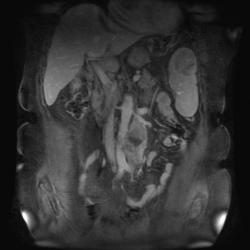

T2 ВИ Sagittal